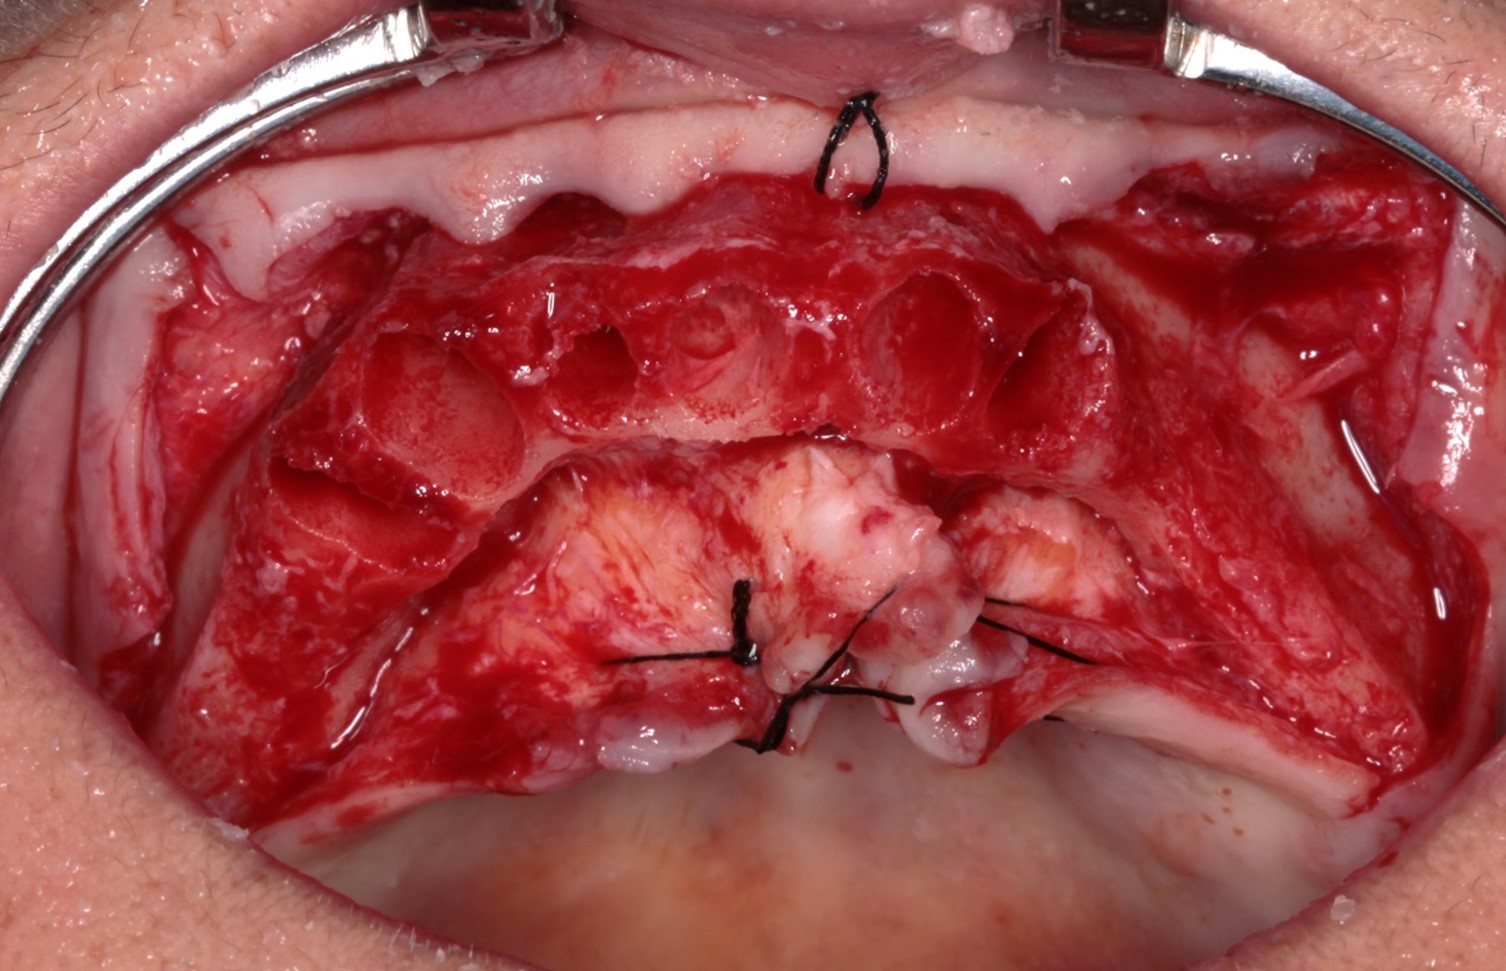

FIG. 03 – Aspecto pós-descolamento do tecido e osteotomia para regularização óssea.

Na análise radiográfica, constatou-se pneumatização do seio maxilar direito em direção ao pilar canino. No lado esquerdo, a extensão da pneumatização poderia inviabilizar a realização da técnica sem enxertos ósseos. Para garantir a instalação precisa e segura do implante, foi realizado um acesso lateral à janela do seio maxilar, permitindo o tratamento da parede anterior do seio com uma sonda para determinar a posição ideal do implante distal. Aproveitou-se o máximo de osso disponível, tangenciando o seio maxilar e eliminando a necessidade de enxertos ósseos. Foi escolhido o sistema Vezza da FGM, devido a geometria que fornece alta estabilidade primária e oferece conexão hexagonal externa universal, ou seja, bastante versátil.

Após a perfuração inicial com broca lança de 15 mm para os implantes distais e 11 mm para os anteriores, a perfuração com broca 2,4 nos mesmos comprimentos. paralelizadores foram utilizados para verificar o polígono formado e a posição dos implantes. A perfuração seguinte com broca 3.4 e, após, com broca 3.9, a onde foi realizado subperfuração em comprimento (50%), garantindo melhor estabilidade primária. Foram instalados implantes Vezza de 4,3×15 mm na região posterior da maxila e de 4,3×11 mm na região anterior.

Todos os implantes atingiram um torque de 80 N, possibilitando a realização de carga imediata. Mini pilares retos com transmucoso de 2mm foram instalados nos implantes anteriores e mini pilares angulados de 30 graus com transmucoso de 3mm nos distais, corrigindo a ajuste dos implantes e sustentando o assentamento passivo da barra.